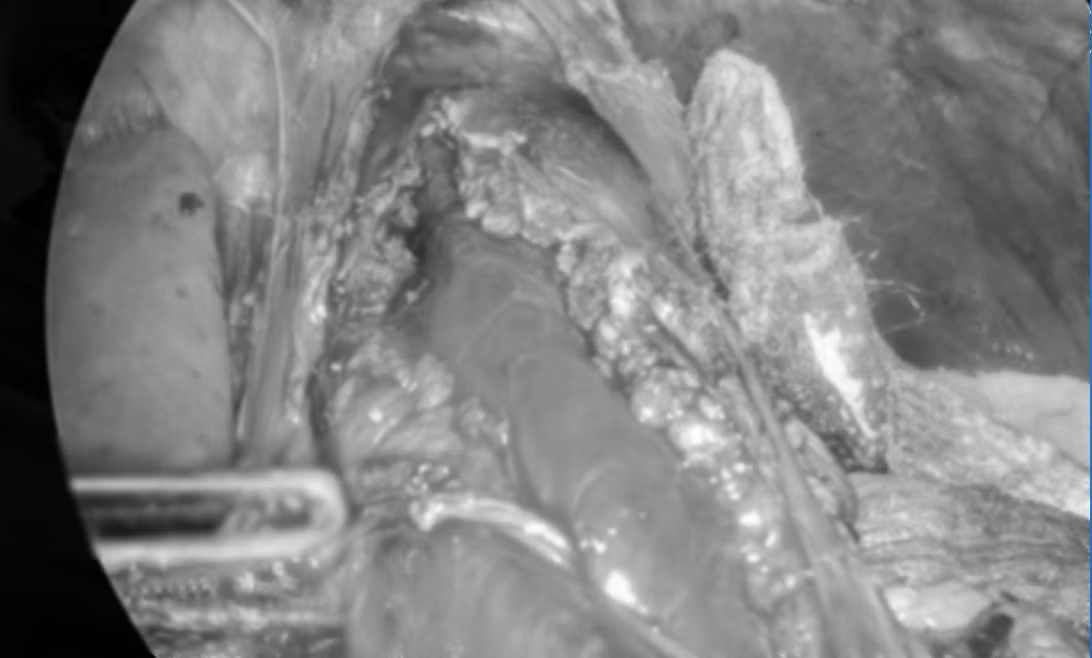

Cuộc phẫu thuật kéo dài gần 2 giờ đã được thực hiện thành công với kỹ thuật cắt dọc lớp cơ ở vùng tâm vị và một phần thực quản, đồng thời tạo van bán vòng trước bằng đáy vị để ngăn ngừa biến chứng trào ngược sau mổ.

tam-vi-1.jpg

Tạo hình thực quản - Ảnh BVCC